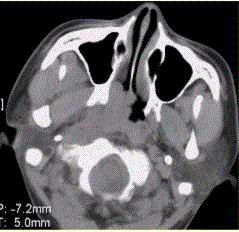

问题 患者男,45岁,鼻塞、涕中带血2周。查体颈部淋巴结增大。专科检查发现,鼻咽腔黏膜肿胀,左侧咽隐窝消失。CT表现如下图。 临床拟诊为

选项 A.鼻窦炎 B.内翻性乳头状瘤 C.纤维血管瘤 D.鼻咽癌 E.淋巴瘤 F.鼻息肉

答案 D